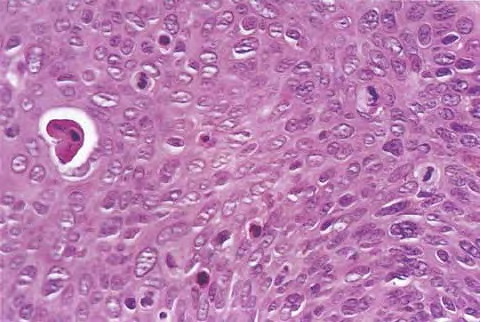

Squamous Cell Carcinoma = الكارسينوما شائكة الخلايا